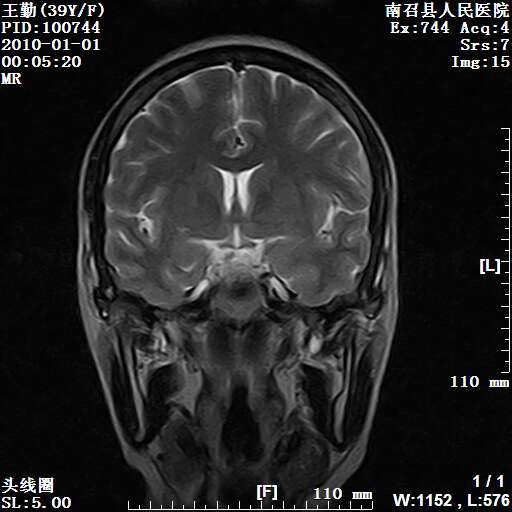

以下是引用随光逐影在2010-1-22 9:03:00的发言:[br]考虑左侧中颅窝(蝶骨翼区)脑膜瘤侵犯蝶骨翼并突入左侧眼眶。

以下是引用水过无痕在2010-1-22 14:55:00的发言:[br]一、定位:颅外占位;二、定性:恶性可能性大;三、组织来源:来源于左侧眼外直肌或其他部位;考虑为:横纹肌肉瘤>转移瘤>脑膜瘤.